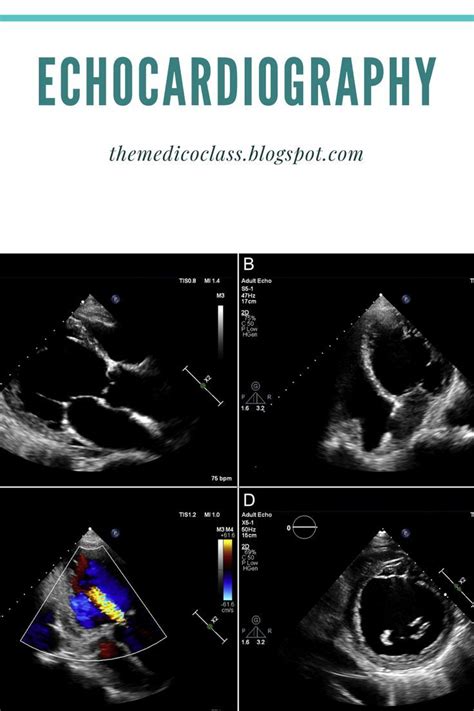

Echocardiography Views Explained

Hey guys! Ever wondered what all those different angles and pictures mean during an echocardiogram? You’re in the right place! We’re diving deep into the fascinating world of echocardiography views , breaking down what they are, why they’re super important, and how they help doctors get a crystal-clear picture of your heart. Think of these views as different windows into your heart’s incredible engine, each offering a unique perspective to help diagnose and manage heart conditions. Whether you’re a medical student, a curious patient, or just someone who likes to understand their health better, this guide will illuminate the essential echocardiographic views you need to know. We’ll cover the standard views, what they show us, and why they’re the bedrock of cardiac ultrasound interpretation. So, grab a coffee, get comfy, and let’s start exploring the amazing insights these views provide!

Alright, let’s get down to brass tacks. Why do we even need multiple echocardiography views ? It’s like trying to understand a complex sculpture; you wouldn’t just look at it from one side, right? You’d walk around it, get different angles, see how the light hits it from various points. The heart is infinitely more complex than any sculpture, and each view in an echocardiogram gives us a specific slice or perspective. These views are crucial because they allow the sonographer and the interpreting physician to assess different parts of the heart, including the chambers, valves, walls, and major blood vessels, in a systematic and comprehensive manner. Without these varied perspectives, we’d miss vital details, leading to potential misdiagnoses or incomplete evaluations. The standard views are meticulously chosen to cover all aspects of cardiac function and structure. For instance, one view might give us a fantastic overview of the entire heart, while another zooms in on a specific valve’s movement. This layered approach ensures that nothing is overlooked, from the subtle fluttering of a valve leaflet to the more significant changes in heart muscle thickness or the flow of blood through the chambers. The goal is always to get a 3D understanding of a 3D organ, and multiple 2D views are our best tool for achieving this. Think about it – how do you know if something is truly enlarged? You need to measure it from different dimensions. How do you assess if a valve is leaking? You need to see its motion and the blood flow across it from multiple angles. That’s where the magic of different echocardiographic views comes into play. They are the standardized language of cardiac ultrasound, ensuring consistency and accuracy in cardiac assessment across different practitioners and institutions.

Now, let’s get into the nitty-gritty of the most commonly used views, especially in a transthoracic echocardiogram (TTE), which is the standard ultrasound done from outside your chest. These views are the bread and butter for most cardiac assessments. We’ll break them down one by one, focusing on what you see and why it’s important. Think of these as your essential checklist for understanding a basic echo report.